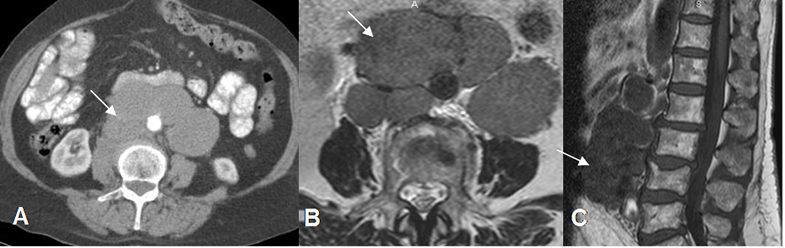

Fig 185. Linfoma.

A: TAC axial, B: RM axial en T2 y C: RM sagital en T1. Gran cúmulo de adenopatías retroperitoneales, que rodean mas del 50% de la circunferencia de la aorta, por linfoma. Están en íntimo contacto con el cuerpo vertebral, pero sin comprometerlo.